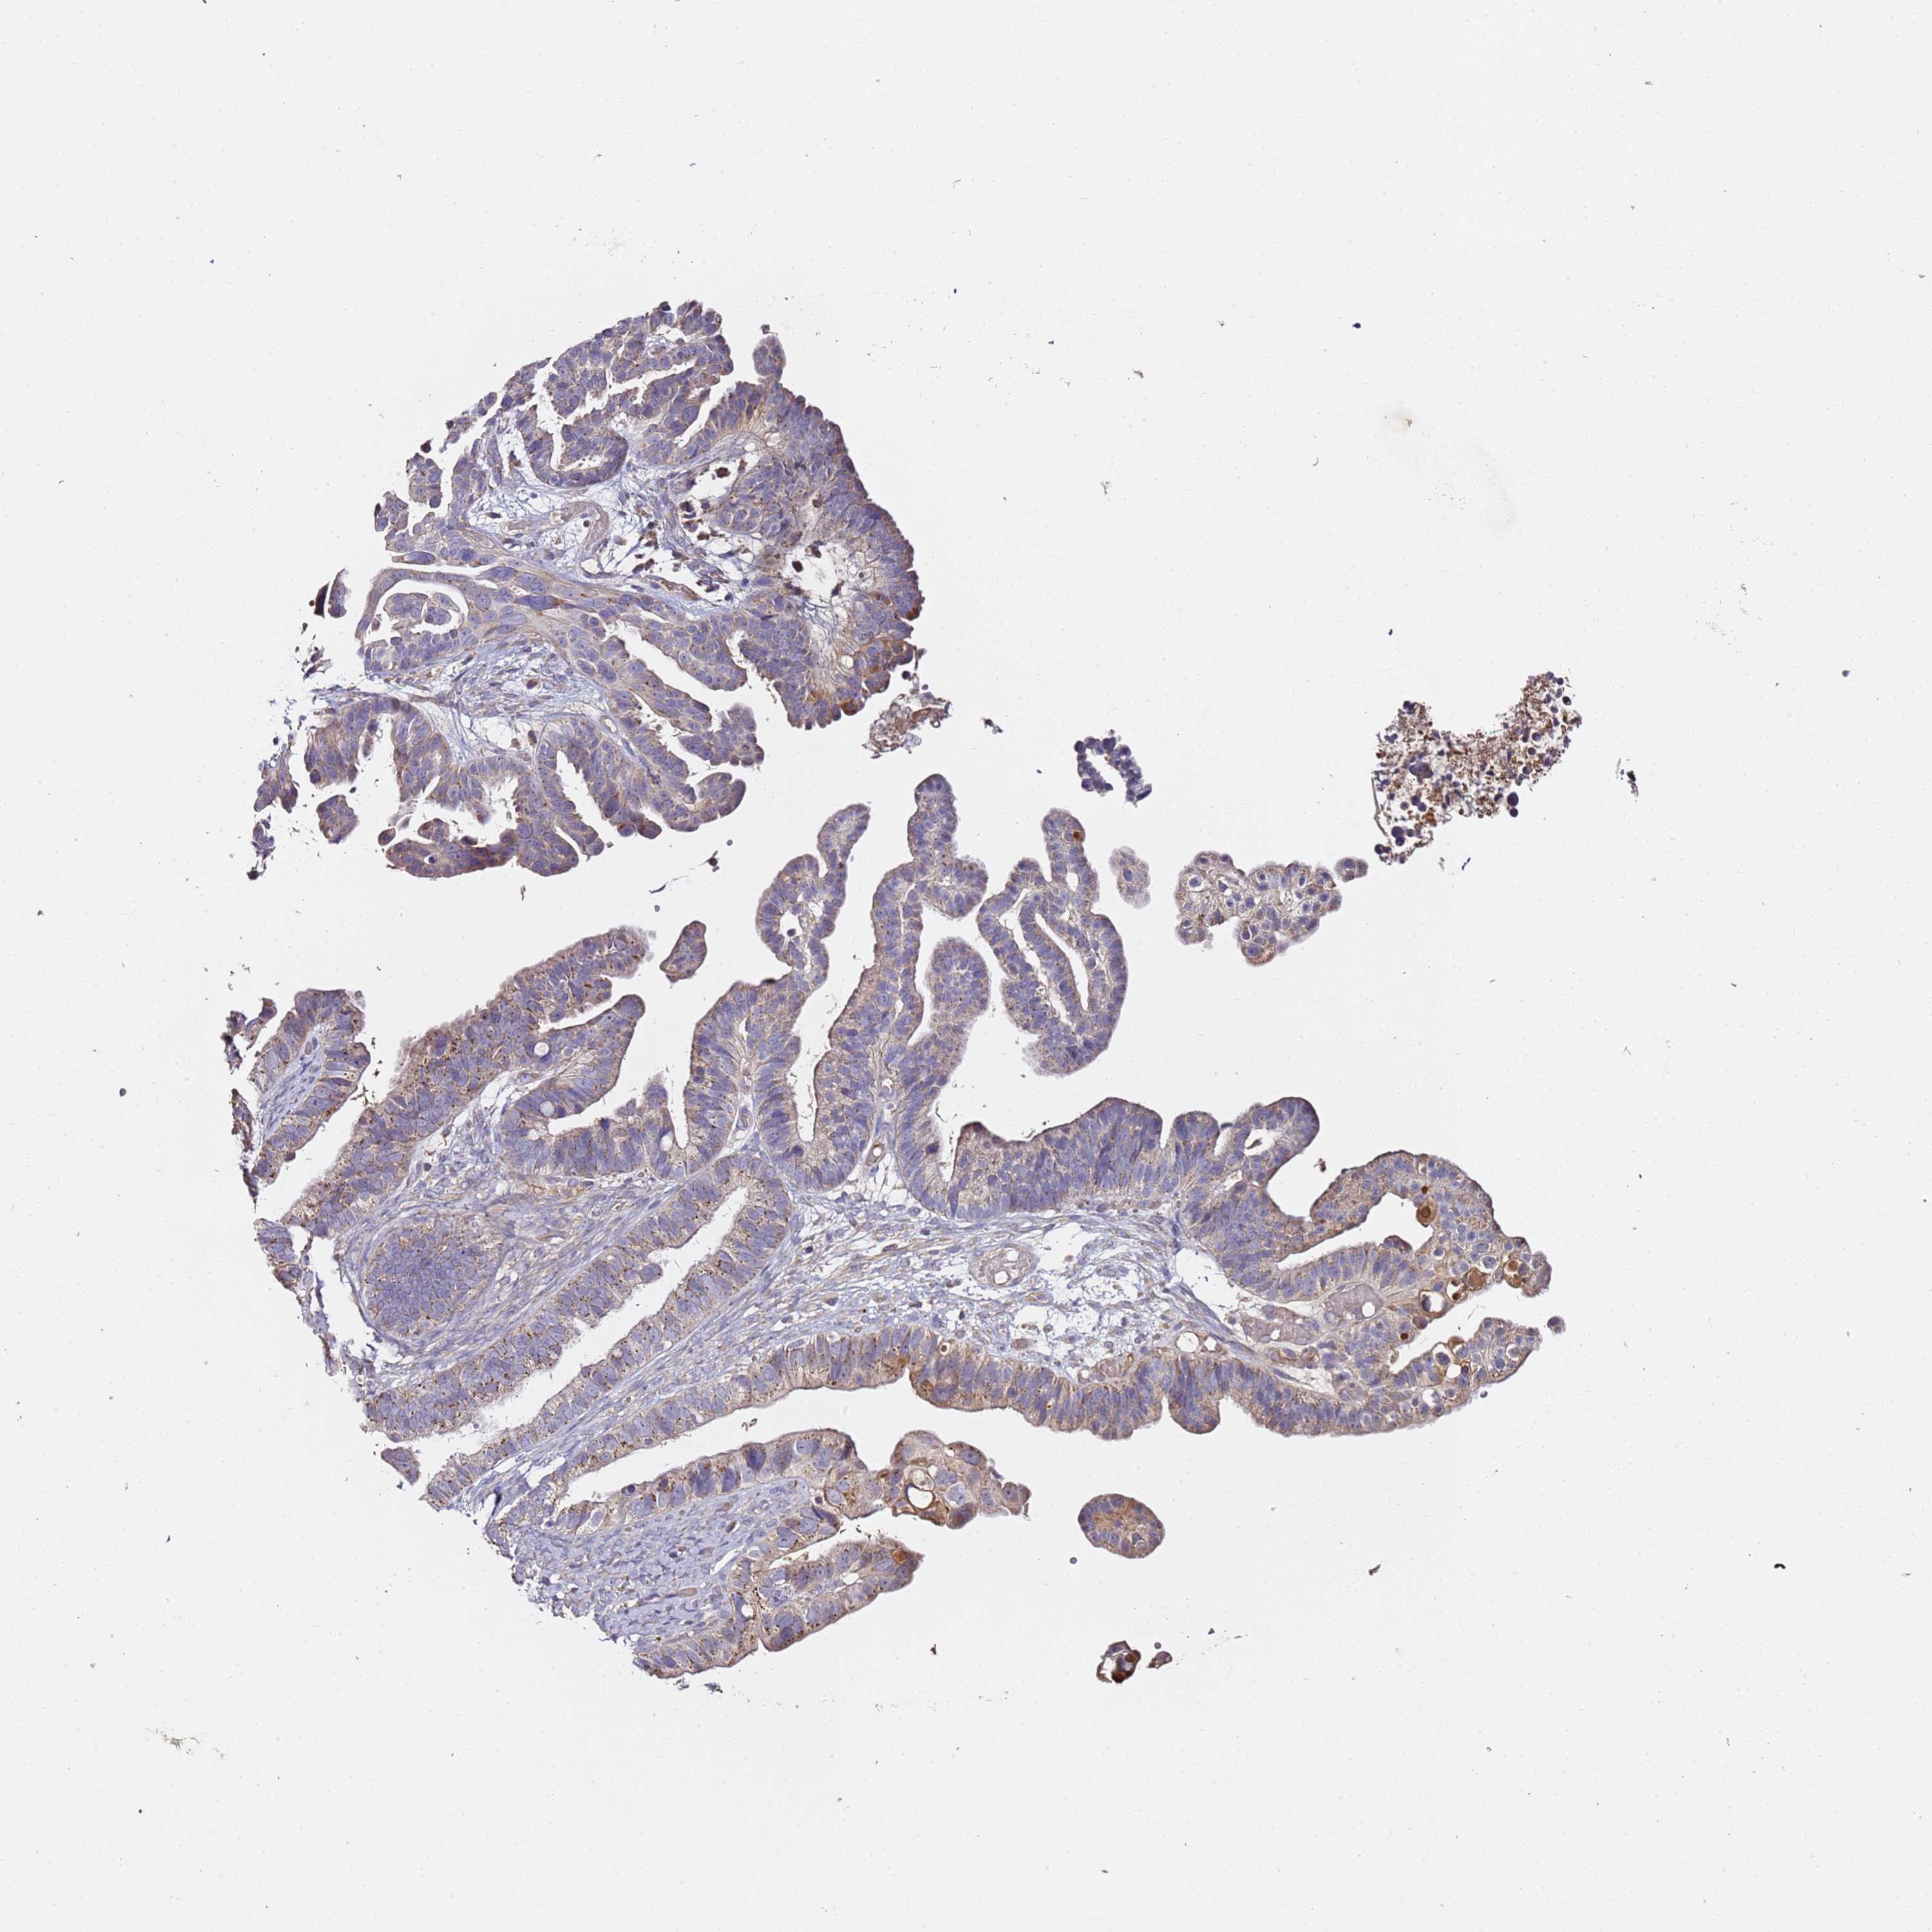

OVARIAN CANCER - Protein expressioni

A mouse-over function shows sample information and annotation data. Click on an image to view it in a full screen mode. Samples can be filtered based on level of antibody staining by selecting one or several of the following categories: high, medium, low and not detected. The assay and annotation is described here.

Note that samples used for immunohistochemistry by the Human Protein Atlas do not correspond to samples in the TCGA dataset.

Antibody stainingi

Antibody staining in the annotated cell types in the current human tissue is reported as not detected, low, medium, or high, based on conventional immunohistochemistry profiling in selected tissues. This score is based on the combination of the staining intensity and fraction of stained cells.

Each image is clickable and will lead to virtual microscopy that enables deeper exploration of all samples and also displays staining intensity scores, fraction scores and subcellular localization as well as patient and tissue information for each sample.

Antibody HPA047459

Staining

High

Medium

Low

Not detected

Intensity

Strong

Moderate

Weak

Negative

Quantity

>75%

75%-25%

<25%

None

Location

Nuclear

Cytoplasmic/membranous

Cytoplasmic/membranous,nuclear

Cystadenocarcinoma, serous, NOS

Carcinoma, endometroid

Cystadenocarcinoma, mucinous, NOS

Carcinoma, NOS